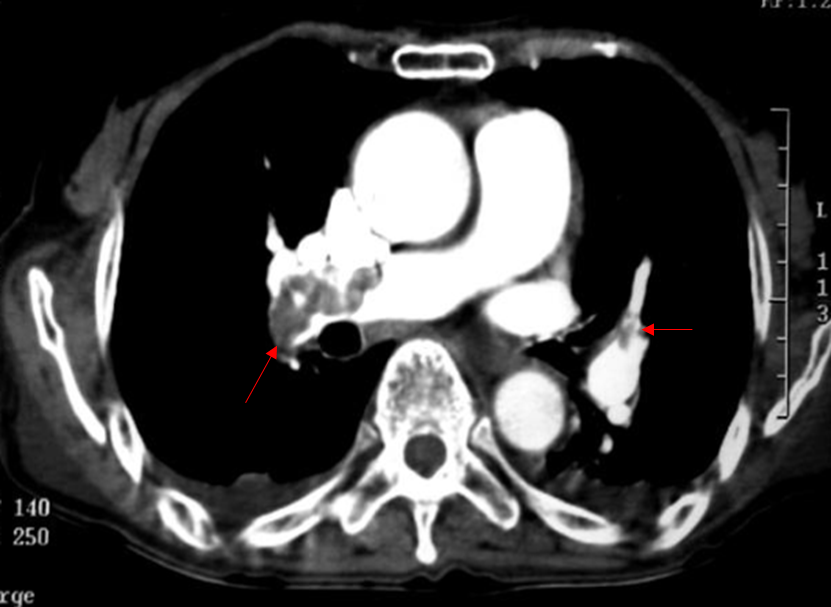

Img | CT: Thrombus at both pulmonary arteries |

• CT상 pulmonary artery 내부에 저음영으로 나타나는 thrombus가 multifocal하게 확인된다. 따라서 PTE로 진단한다.